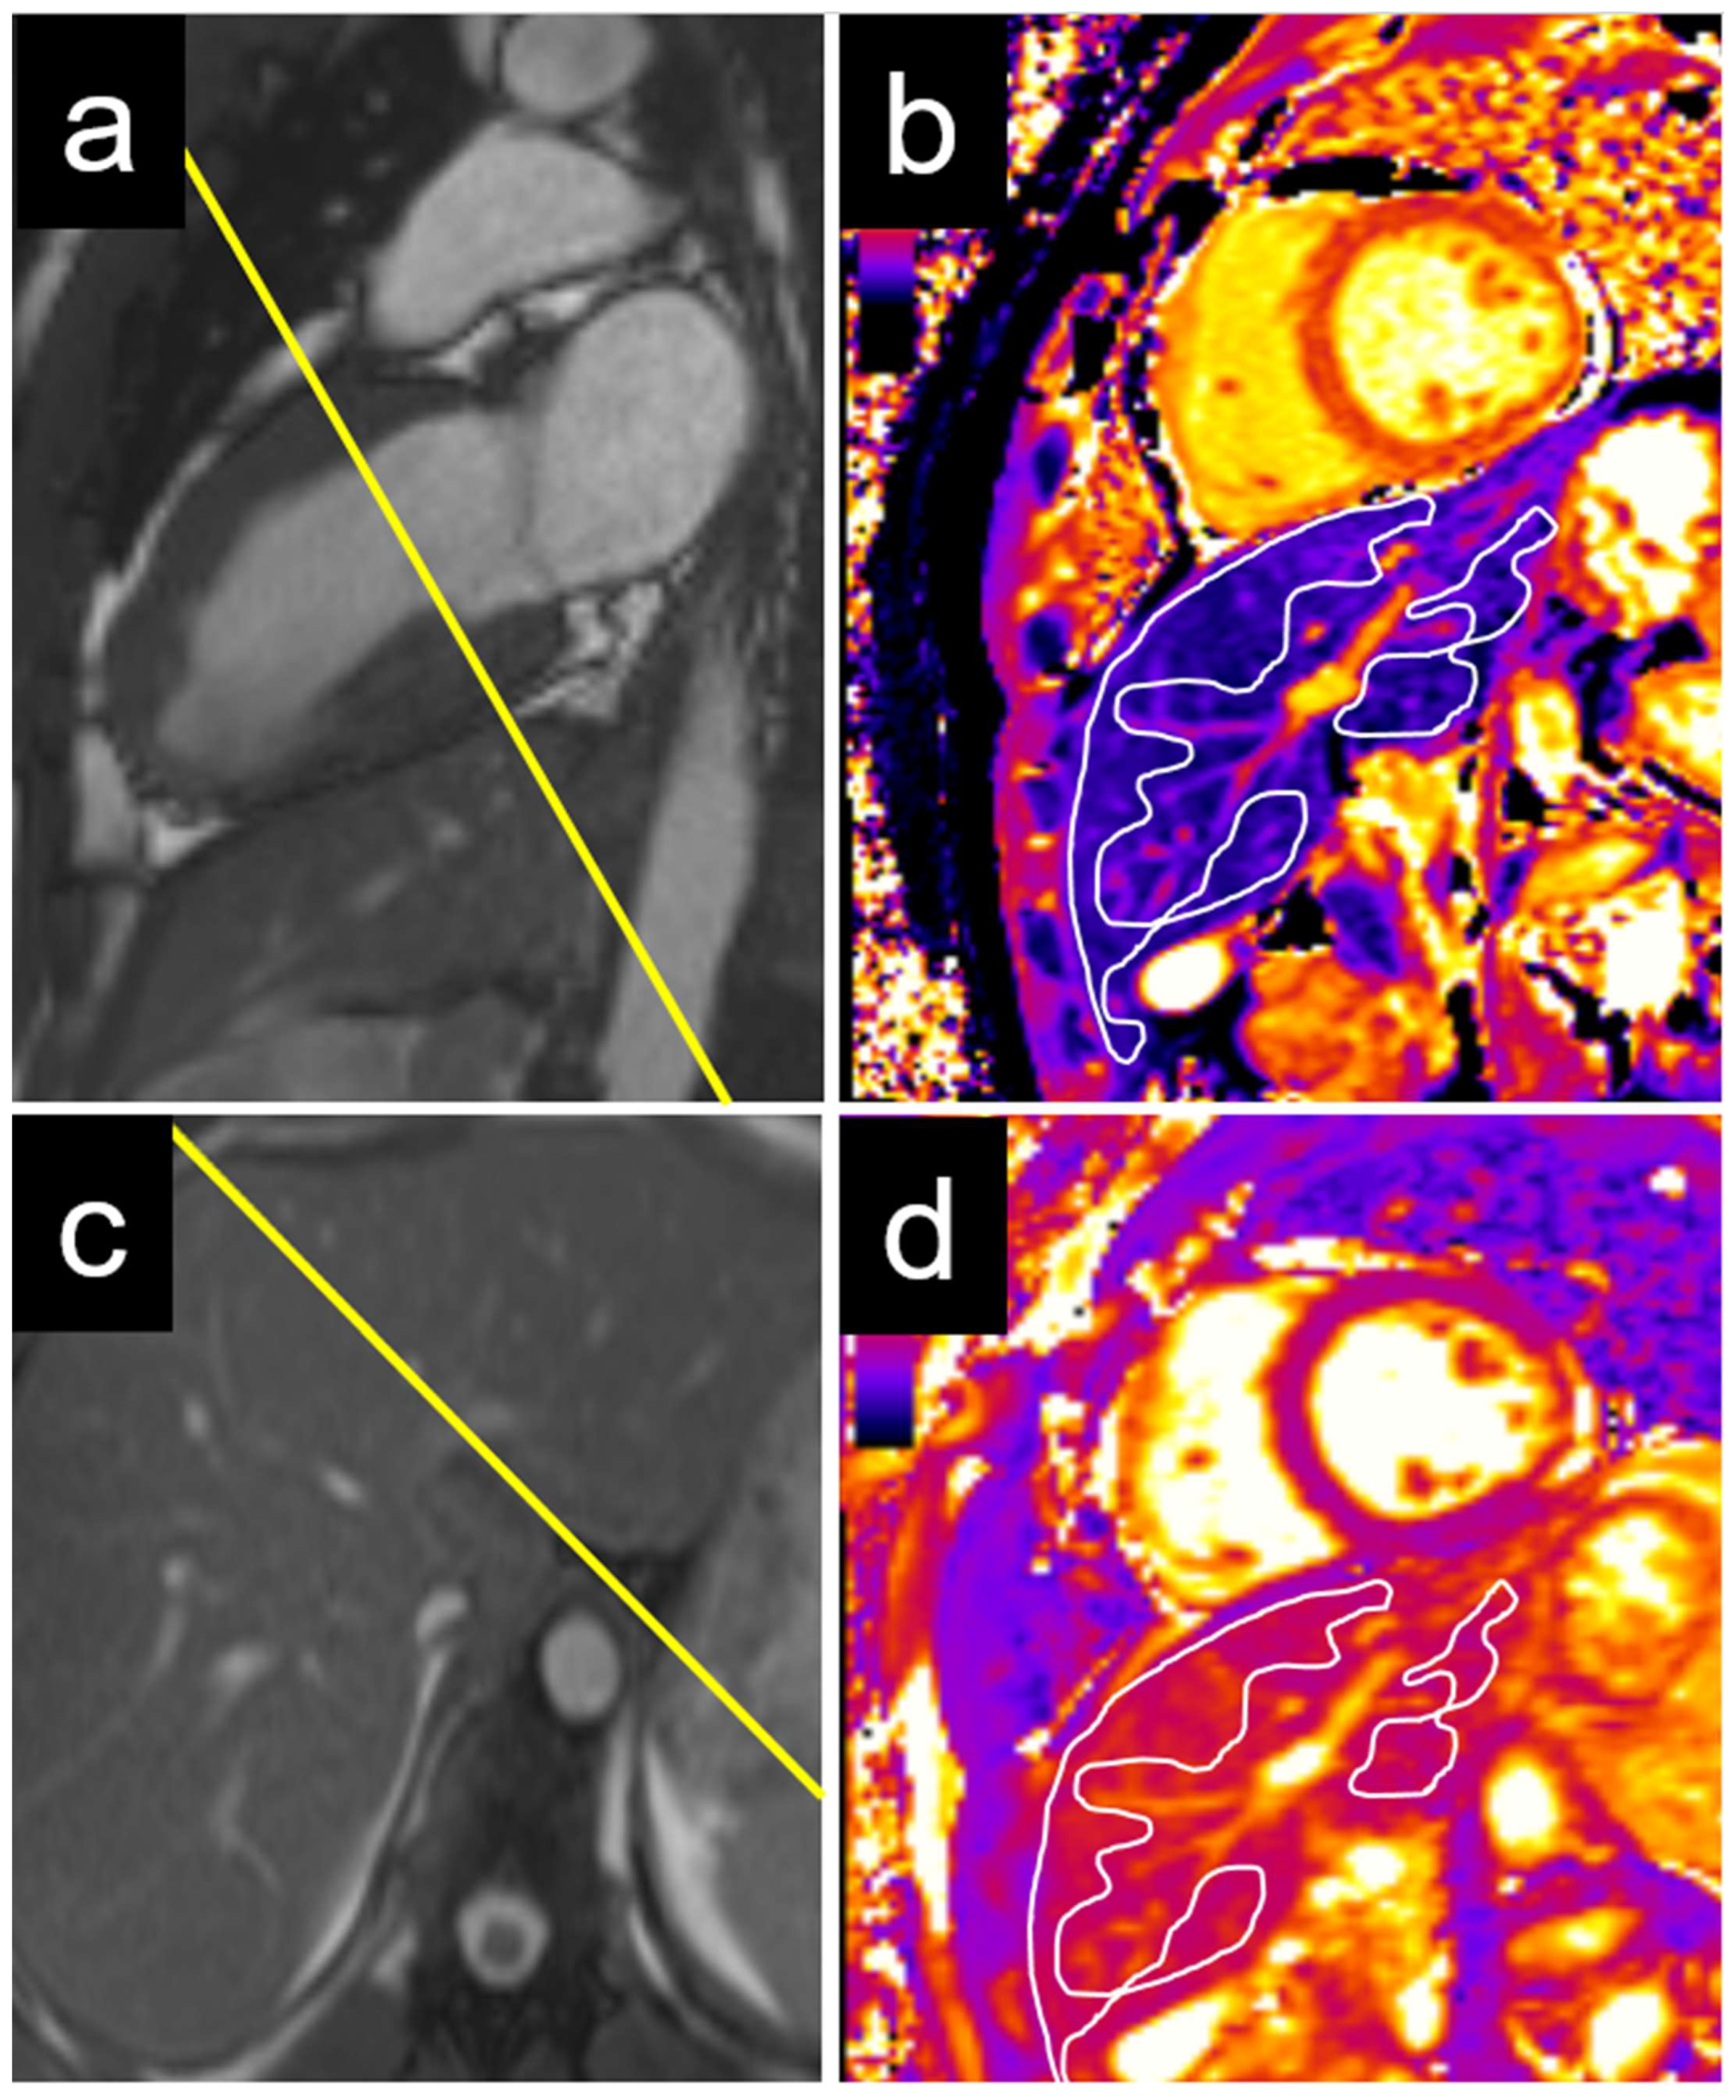

2.3. Cardiac Magnetic Resonance Imaging Protocol

2.5. Cardiac MRI Analysis